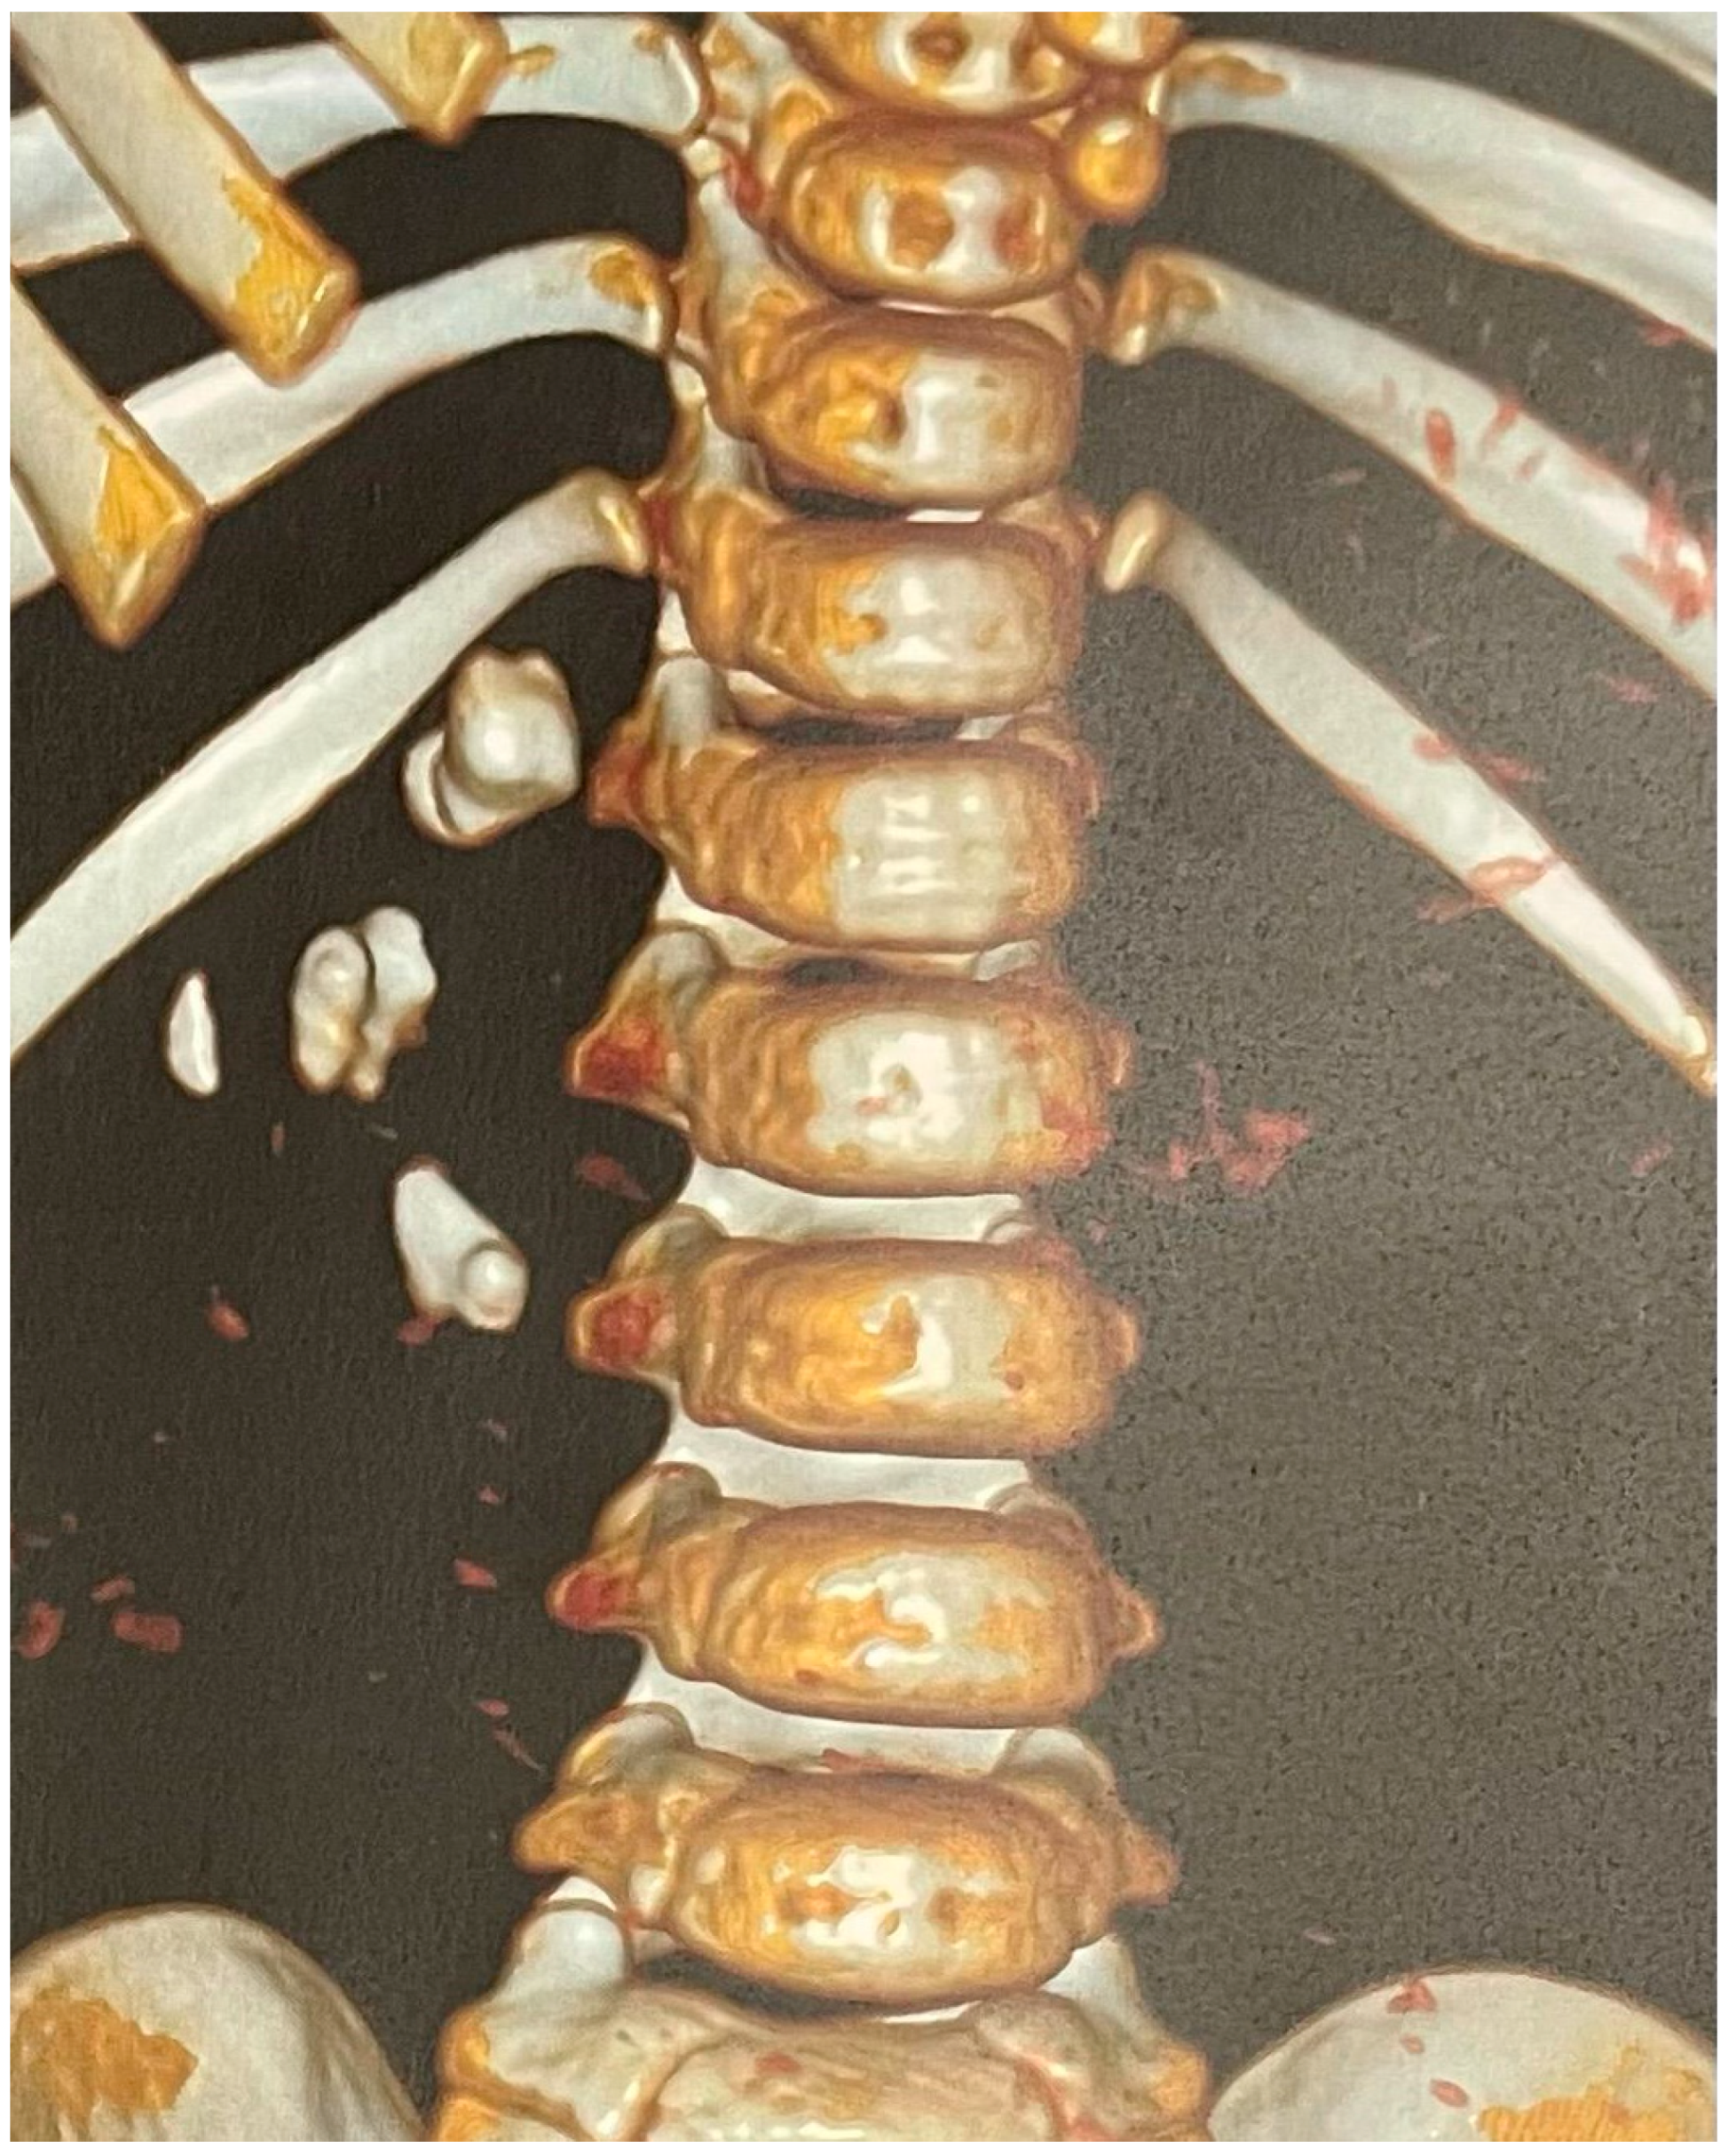

A non-contrast low-dose kidney–ureters–bladder (KUB) computed tomography (CT) was performed, reporting six stones in the right kidney of the patient with a cumulative stone burden of 3.2 cm2 (two stones per calyx without filling the pelvis). The largest stone was located in the upper calyceal system, measuring 10 × 14 mm and 810 Hounsfield units (HUs) (Figure 1 and Figure 2).

Figure 2. The 3D reconstruction of the preoperative CT scan of this case showing the stones in the right kidney.